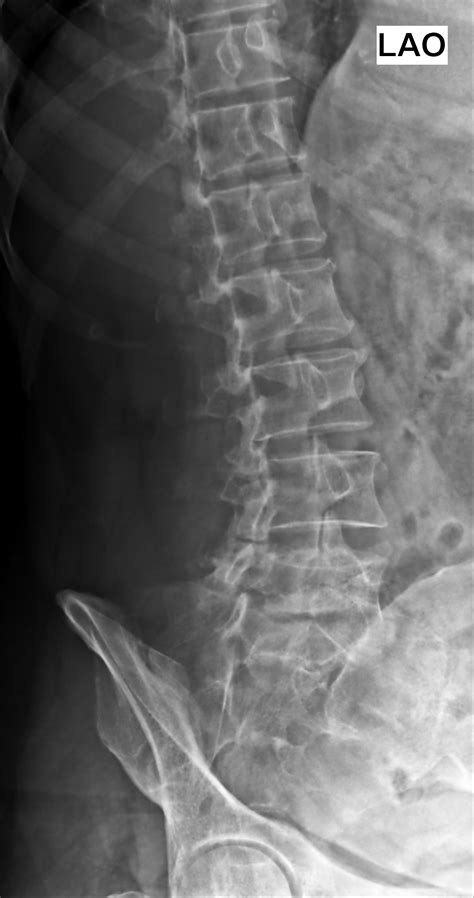

Diagnosing Spondylolisthesis Grade 1

Diagnosing Spondylolisthesis Grade 1 involves a combination of medical history, physical examination, and imaging tests. The diagnostic process typically includes:

• Imaging Tests: X-rays, CT scans, and MRI scans are commonly used to visualize the spine and determine the degree of slippage.

Imaging tests are particularly important for confirming the diagnosis and assessing the severity of the condition. X-rays can show the alignment of the vertebrae, while CT scans and MRI scans provide detailed images of the soft tissues and nerves.